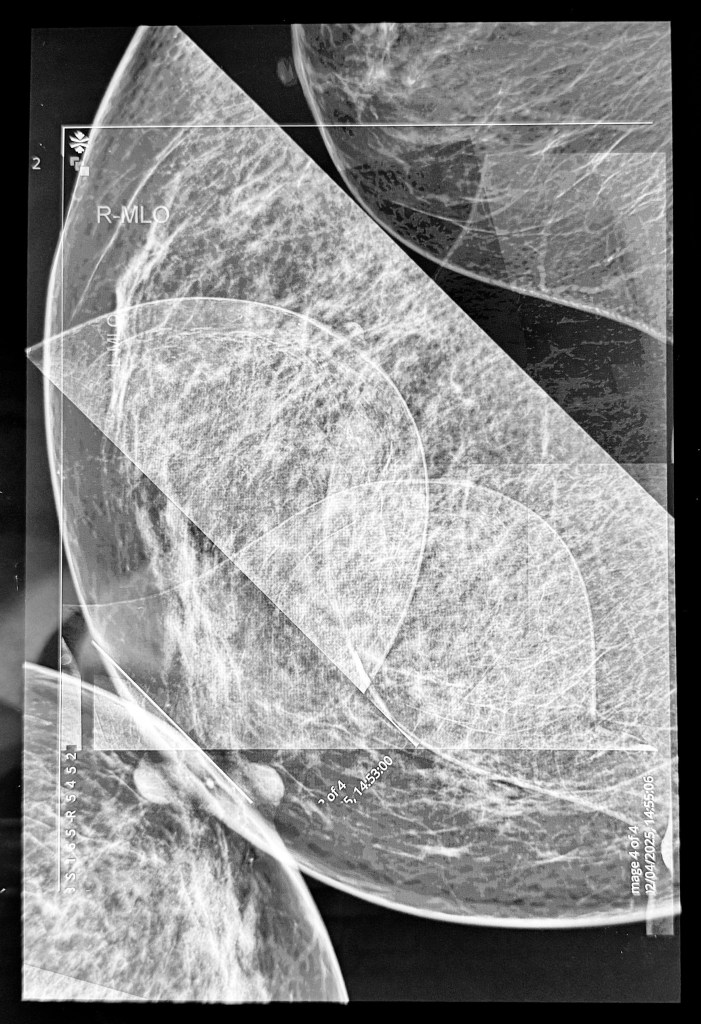

I took all four images: right and left mediolateral oblique and right and left craniocaudal. I removed my personal info and removed some digits from my hospital number as I wanted it to be apparent that they are medical images. I then imported them into Procreate and played around with inverting and layering etc. And this is when I learnt an important lesson – whilst it’s great to experiment and try lots of different things, if you don’t make a note of it somewhere you won’t be able to recreate it. I liked the first image I made but wanted to adjust some of the transparency in some areas. So I adjusted it but couldn’t remember what I had done to create the final image. Try as I might I just couldn’t recreate it so, in the end, I decided to run with the original image. I displayed the image on my laptop screen and then took a photograph of it which incorporated some of the reflections on the screen, which I think add a bit of depth and additional interest to the image. The idea was to print it and then overdraw with pencils, charcoal etc. I experimented on a home-printed image. I became even more despondent because nothing seemed to work. I decided to fold it, scrunch it and cut it up. Then I thought, a good approach when something isn’t working is to cut it into strips and weave it. I liked the effect, and my mood lifted.

Anyway, when I got the A3 image from the printers I didn’t think it was that bad, and I couldn’t bring myself to cut it up so I just overdrew some areas adjusting tones using black, grey and silver pencils and some charcoal. I quite like how the inclusion of the straight lines and the curves suggest a graph of some sort, how it has both a geometric feel but also a natural, landscape feel, as if the line towards the centre is the waterline and beyond is a land mass, the dark area on the left almost reading as a tree. It was rolled up, so I’m going to have to flatten it and sort out proper lighting before I take a photo for submission. I actually really like it.